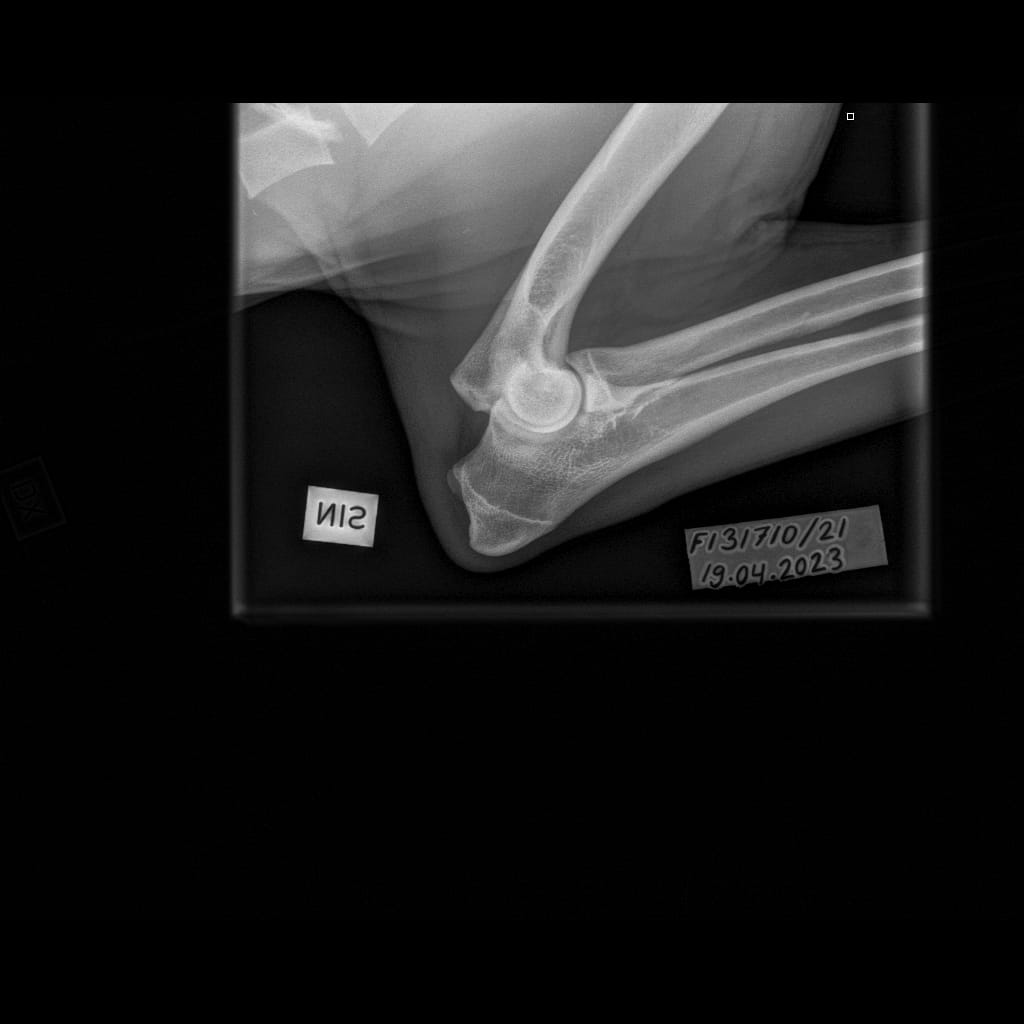

Eturaajat -Kyynärnivel LAT-6.11.2023-16_02_23-281 (1)